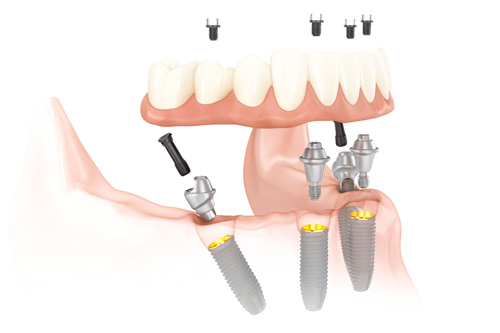

| 固定方法 | 4本のインプラントに連結バーを介し、ブリッジ型の人工歯を固定 |

手術当日:インプラント埋入+即日仮歯セット

静脈内鎮静下(うたた寝状態)で、片顎約2時間ほどの手術を行います。

手術当日に、固定式の仮歯を装着できますので、

「その日のうちに噛める・笑える」ことが可能です。

全てデジタル設計による高精度サージカルガイドを使用します。

最終上部構造(ジルコニア)装着

骨との結合が安定したら、最終的なフルジルコニアの歯を製作・装着します。